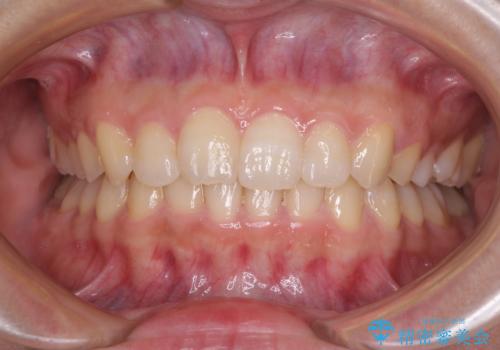

- 前歯のでこぼこと乳歯が残るほどの八重歯を気にして来院された患者様です。

非抜歯にてワイヤー矯正にて治療することとしました。(ただし、親知らずと乳歯は抜歯)

犬歯は歯根が太く長いため、移動には時間を要します。しかし、犬歯は機能面から考えて残すことを選択したいため、長期間をかけて治療を行うこととしました。

治療の度に歯列が改善していったため、長期間の治療も楽しく過ごしていいただき、満足のいく仕上がりとなりました。